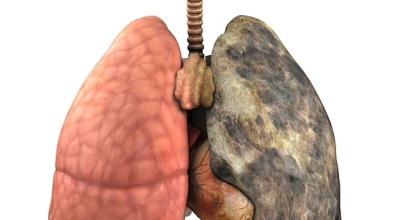

폐에 발생된 악성 종양을 말하며 오랜 기간 흡연해온 남성들에서 발병률이 높고 요즘 들어서 갖가지 환경적인 요인의 영향과 간접흡연으로 흡연하지 않는 여성에서도 많이 발생하고 있답니다. 증상을 느껴 병원을 찾았을 때는 수술하기 늦은 경우가 많아 사망하는 비율이 매우 높은 암입니다. 폐 자체에서 생기거나 다른 장기에서 발생된 암이 폐로 전이되어 나타나기도 하고 특별한 초기 증상이 없는 경우가 많으며 암이 진행된 후에도 일반적인 감기 증상인 기침과 가래 외의 특이 증상이 나타나지않아 증상만으로는 진단이 쉽지 않아요.

폐암의 공통 위험요소로 손꼽히는 이유가 되는 것으로 흡연이 있답니다. 흡연자는 비흡연자에 비교해 십몇 배는 더 폐암 발병확률이 높다고 하며 어느정도 기간 동안 흡연했는지에 따라 폐암 발생확률은 더더욱 더 높아져요. 흡연자라고 해도 금연을 하게 되면 폐암 발병확률이 빠르게 내려간다고 하니 폐암이 걱정되신다면 가장 먼저 금연은 필수입니다.